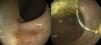

Se realizó una colonoscopia procediendo a la extracción del cuerpo extraño en recto. En dicho procedimiento se objetivó en la cara proximal de la 1.ª válvula de Houston, mediante retroflexión rectal, una depresión puntiforme, compatible con un orificio fistuloso, que no requirió ningún abordaje extra (fig. 2).